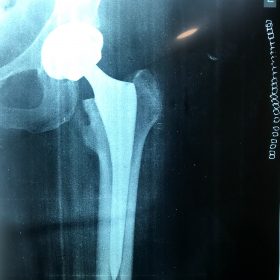

Παραδοσιακά οι αρθροπλαστικές ισχίου αποτελούνται από μια μεταλλική μπάλα – σφαίρα τοποθετημένη σε μια πλαστική κοιλότητα (κοτυλιαία πρόθεση).

Η πλαστική επιφάνεια στήριξης φθείρεται με την πάροδο του χρόνο, με ρυθμό μάλλον σχετιζόμενο με το επίπεδο δραστηριότητας του ατόμου. Αυτό έχει σαν επακόλουθο νεότεροι ασθενείς με μεγαλύτερο προσδόκιμο ζωής να έχουν αυξημένο ρίσκο αναγκαιότητας δεύτερης αρθροπλαστικής ισχίου (αναθεώρησης – Revision) επέμβαση που είναι πολυπλοκότερη και υπόκεινται σε υψηλότερο κίνδυνο επιπλοκών. Βάση των ανωτέρω, ιστορικά, η αρθροπλαστική ισχίου σπανίως εφαρμοζόταν σε ασθενείς κάτω των 60 ετών.

Χάρη στα νέα τεχνολογικά επιτεύγματα έχουν παραχθεί επιφάνειες στήριξης που ανταποκρίνονται σε μεγαλύτερα επίπεδα δραστηριότητας και αναμένεται να έχουν μεγαλύτερη διάρκεια ζωής. Αυτές οι καινούριες επιφάνειες στήριξης είναι συνήθως μέταλλο πάνω σε ειδικό σκληρότερο πλαστικό ή κεραμικό πάνω σε κεραμικό. Ως εκ τούτου, είναι τώρα πολύ πιο σύνηθες, νεότεροι ασθενείς να χειρουργούνται καθώς η πλειονότητα αυτών, που η αρθρίτιδα τους προκαλεί αφόρητους πόνους, επιλέγουν να έχουν ποιότητα ζωής από το να ζουν με τον πόνο.

Η αρθροπλαστική ισχίου αποτελεί μια αποτελεσματική επέμβαση αποκατάστασης και πρέπει να εφαρμόζεται μόνο όταν οι ασθενείς δεν είναι σε θέση να αντέξουν άλλο τον πόνο και την ανικανότητα και εφόσον τα πλεονεκτήματα καθώς και οι πιθανοί κίνδυνοι της μεθόδου έχουν εξηγηθεί πλήρως από το χειρουργό και έχουν κατανοηθεί από τον ασθενή.